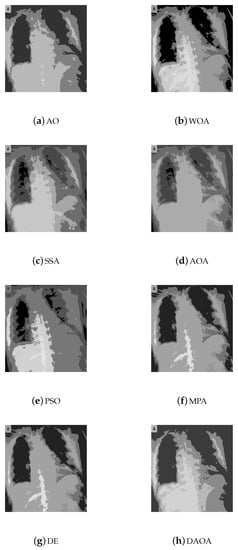

4.1. Benchmark Images

4.3. Performance Evaluation